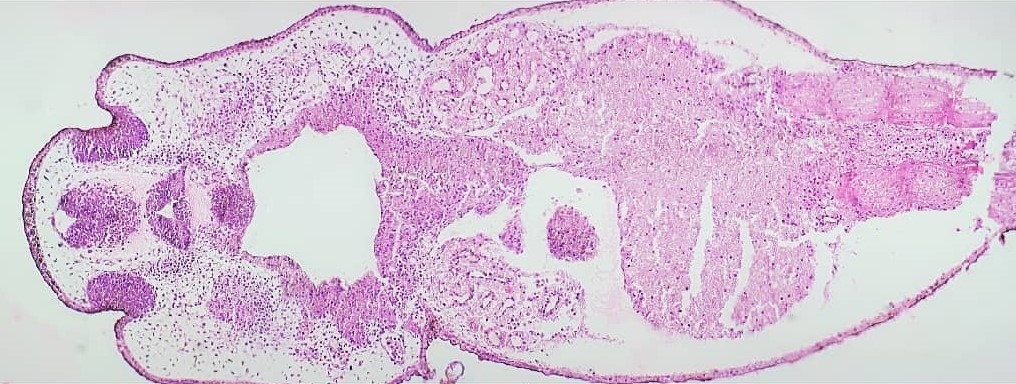

In diesem Artikel zeige ich Schnitte durch eine frisch geschlüpfte Kaulquappe. Man erkennt die Entwicklung einiger Organe. Ich bin bei weitem kein Embryologie-Experte und für Ergänzungen/Korrekturen dankbar. Dieses sehr frühe Stadium der Entwicklung ist der Embryonalentwicklung des Menschen sehr ähnlich.

Der Schwanz fehlt, da die Kaulquappe bei der Entnahme schon tot war und keinen Schwanz mehr hatte.

Übersichtsaufnahme

1 - Riechgrube

2 - Telencephalon

3 - Hirnnervenkerne

4 - Cerebellum

5 - Somiten

6 - Pharynx